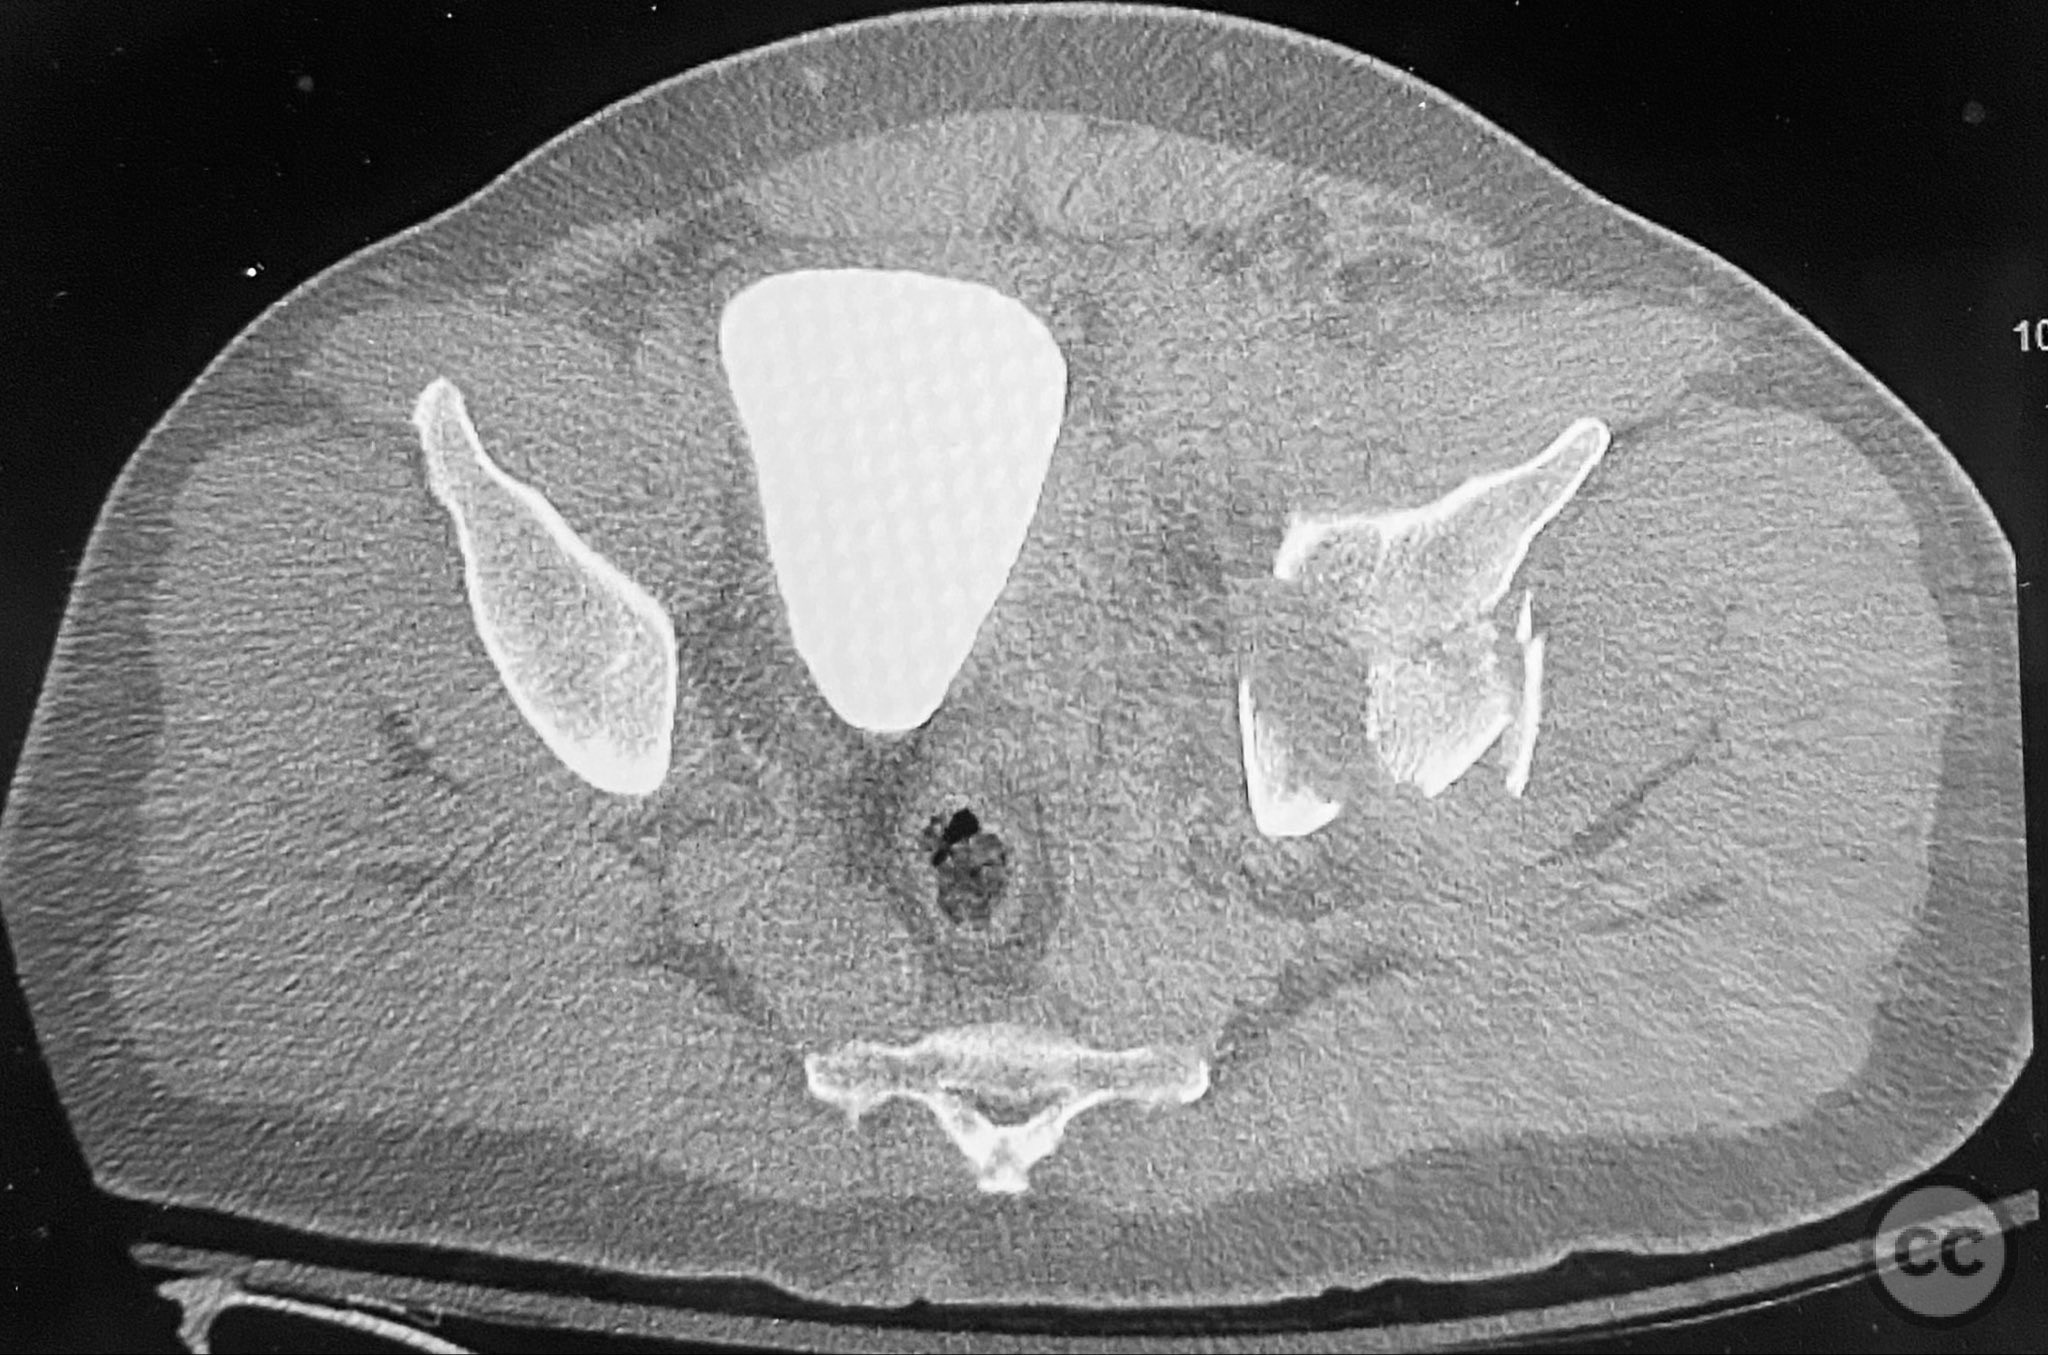

acetabulum fracture

türkiye, Turkey

Pelvis - AO/OTA 6x